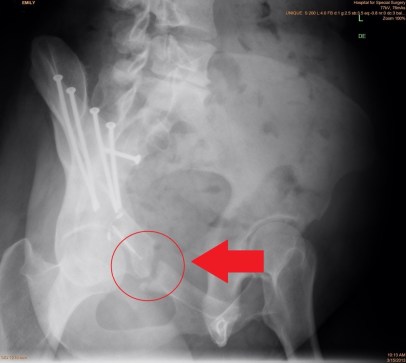

This recovery has been going extremely well, my pain managed by Tylenol, and my surgeon was pleasantly surprised at how well I was doing. I mentioned that when I stopped my narcotic medication and switched to OTC meds, I had some unpleasant withdrawal symptoms including extreme irritability, insomnia, and two days of crying for seemingly no reason (must remember for future reference to avoid this medication). I explained how the pain in my left side is more of a deep muscle ache that is always noticeable but not severe or excruciating. The pain on the right side, the side in which I had the PAO surgery in December, is actually where I noticed the more striking and alarming pains. We had previously discussed, before the second surgery, that this would likely be the case . The right side still has problems though the extent is not yet clear. My doctor noted there is always a chance, unfortunately, that once one problem is fixed, another may become unmasked. For example, it’s possible that once the dysplasia in my right side was fixed with the December PAO surgery, impingement may have been unmasked and that may be causing the pain I continue to have in the right side. Similarly, it is possible that, now that the impingement on my left side has been repaired with the SDD surgery, the dysplasia related to my acetabular retroversion may become more prominent.

As you can imagine, I am hopeful that I am finished with surgeries and that physical therapy will help take me to the finish line in terms of recovery. My next follow-up appointment is scheduled for mid June, at which point my surgeon will take x-rays of my left leg and hip to determine if the trochanter osteotomy he performed is healed and whether I can stop using crutches.